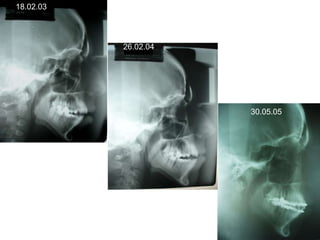

O documento apresenta registros odontológicos de um paciente ao longo de vários anos, incluindo panorâmicas iniciais e subsequentes, remodelações de arcadas dentárias superiores e inferiores ao longo de 7 meses, vedamentos labiais e registros de máxima intercuspidação e guias caninas nas datas listadas.